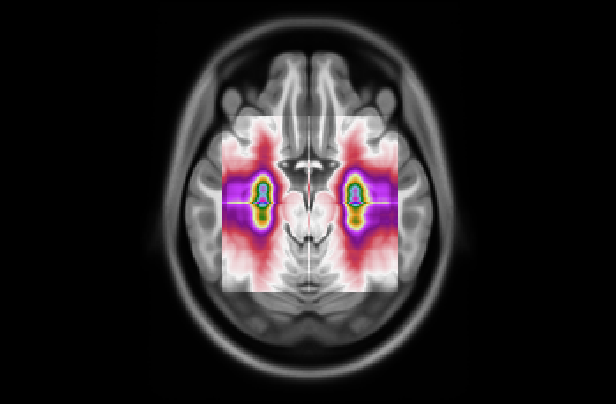

Figure 7: (Left) Attention distribution for each plane averaged on all the five test to provide entire dataset distributions; (Right) Visualization of mean 3D attention map of entire dataset overlapped to MNI152 template

This section analyzes the interpretability of our approach and those proposed in (Wang et al., 2024; Altay et al., 2021). Our XAI method described in Section 4.3 allowed us to produce a 3D attentional map starting from the attentional weight distributions of the axial, coronal, and sagittal planes. The authors of AwareNet (Wang et al., 2024) designed the slice-aware module of this network to extract, as in our case, a distribution of attentional weights capable of summarizing the importance of each slice in the decision-making process. As a result, our approach can produce a 3D map also using the model proposed in (Wang et al., 2024).

This subsection examines the visual results and quantitative analysis concerning the brain areas emphasized by each model. Fig. 7, on the left, displays the attentional weight distributions across the three planes, averaged over all five folds of the cross-validation. This averaging provides a comprehensive view of the data distribution across all images in the dataset. Starting from the entire dataset distributions, the 3D attentional map was created as detailed in Section 4.3. The averaged 3D map was enhanced by a factor of 10 and overlaid on the MNI152 template, which is representative of a typical patient’s brain. Combining this template with its corresponding atlas facilitates the identification of regions that, on average, received attention from the models. The right side of Fig. 7 shows the explainable MRI generated. The visual representation also indicates that the network targets the medial temporal lobe region, as suggested by the distributions. This result is confirmed by the quantitative analysis shown in Table 8, which reports the metrics for the 20 more extensive regions selected by our model and by AwareNet. As shown in Table 8(a), the three largest regions focused by our diagnosis model are the hippocampus, the parahippocampus, and the amygdala. In contrast, the 3D attentional map generated with AwareNet appears to focus on different regions. The first 3 regions highlighted are Cerebellum Gray Matter, Lateral Occipital, and Fusiform. The right part of the hippocampus appears only after them. From this result, it is also possible to note that with the same 99.9 percentile threshold for binarization, our model highlights a much more localized region. Specifically, our model selects 17 regions with a strong concentration in the top 14. On the contrary, AwareNet highlights 88 regions, 68 of which have been omitted in the Table 8.